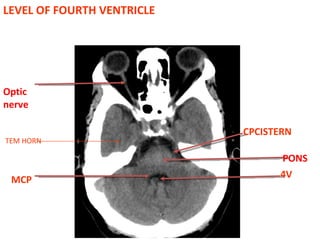

LEVEL OF FOURTH VENTRICLE MCP CPCISTERN PONS 4V TEM HORN Optic nerve

LEVEL OF FOURTHVENTRICLE MCP CPCISTERN PONS 4V TEM HORN Optic nerve